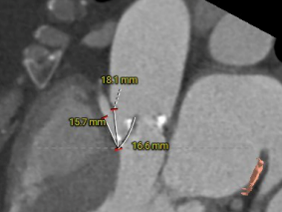

左窦瓣叶长度:15.2mm

右窦瓣叶长度:16.6mm

左冠开口高度:7.1mm

右冠开口高度:13.7mm